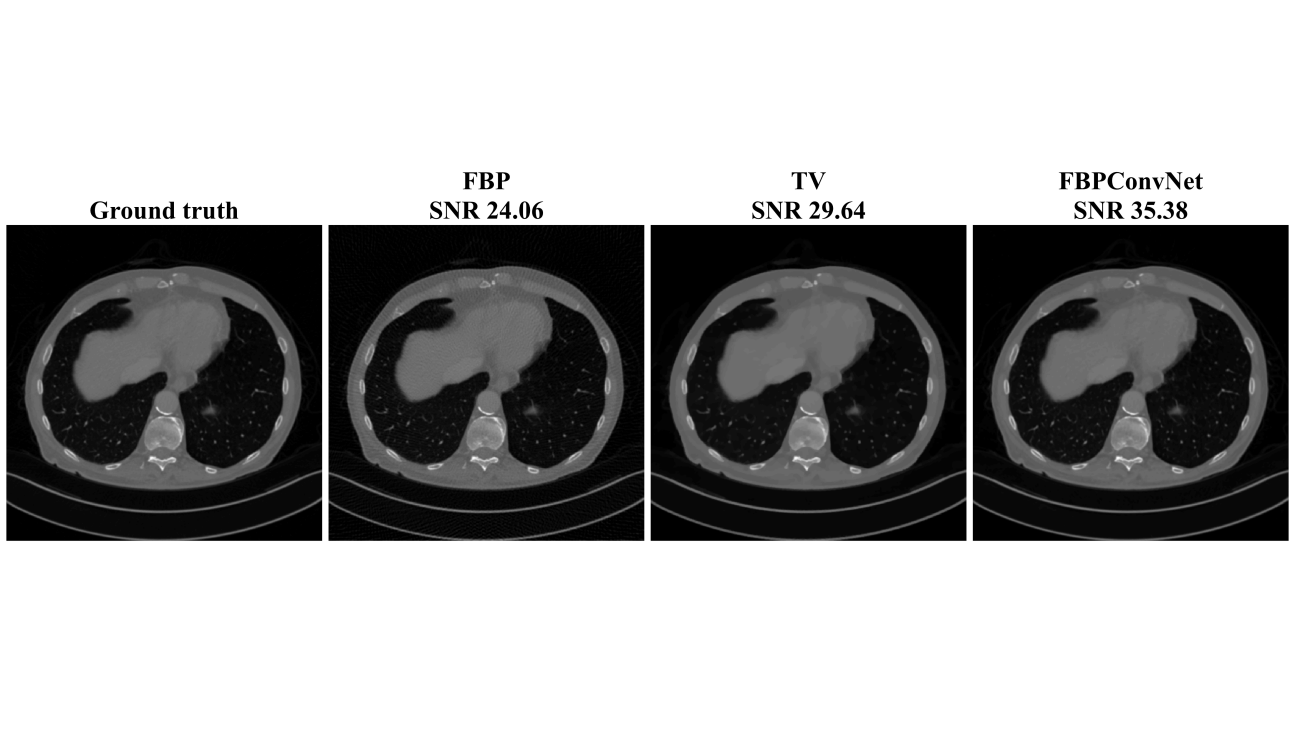

Figures 5 and 6 and Table II show the results for the biomedical dataset. In Figure 5, again, the sparse-view FBP contains line artifacts. Both TV and the proposed method remove streaking artifacts satisfactorily; however, the TV reconstruction shows the cartoon-like artifacts that are typical of TV reconstructions. This trend is also observed in severe case (x20) in Fig. 6. Quantitatively, the proposed method outperforms the TV method.

| avg. SNR (dB) | 143 views (x7) | 24.97 | 31.92 | 36.15 |

| 50 views (x20) | 13.52 | 25.2 | 28.83 | |